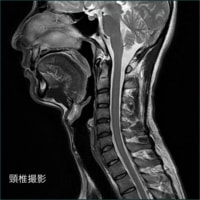

軟部組織のコントラストに優れ、様々なコントラストパラメーターを有するMRIは、頭頚部、体幹部、脊椎・脊髄、整形領域、心臓領域とほぼ全身に渡る断層画像をあらゆる角度で撮像できます。

MRIの画像